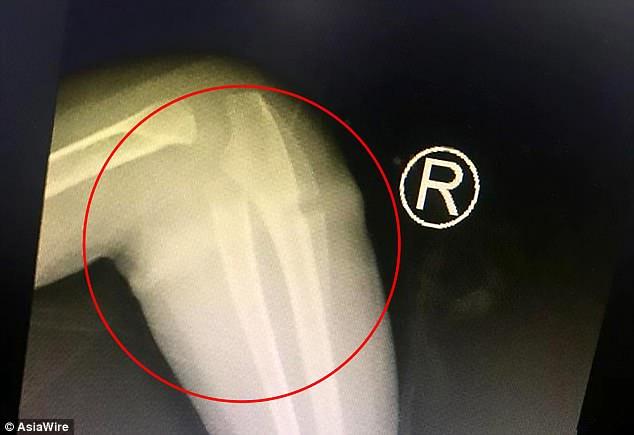

Μετά από έναν υπέρηχο Β σάρωσης οι γιατροί είπαν στους γονείς της μικρής ότι το πρήξιμο και ο πόνος οφείλονταν στο λαστιχάκι που είχε ενσωματωθεί στο δέρμα της.

Χρειάστηκε να γίνει μια επέμβαση 30 λεπτών για να αφαιρεθεί το λαστιχάκι.